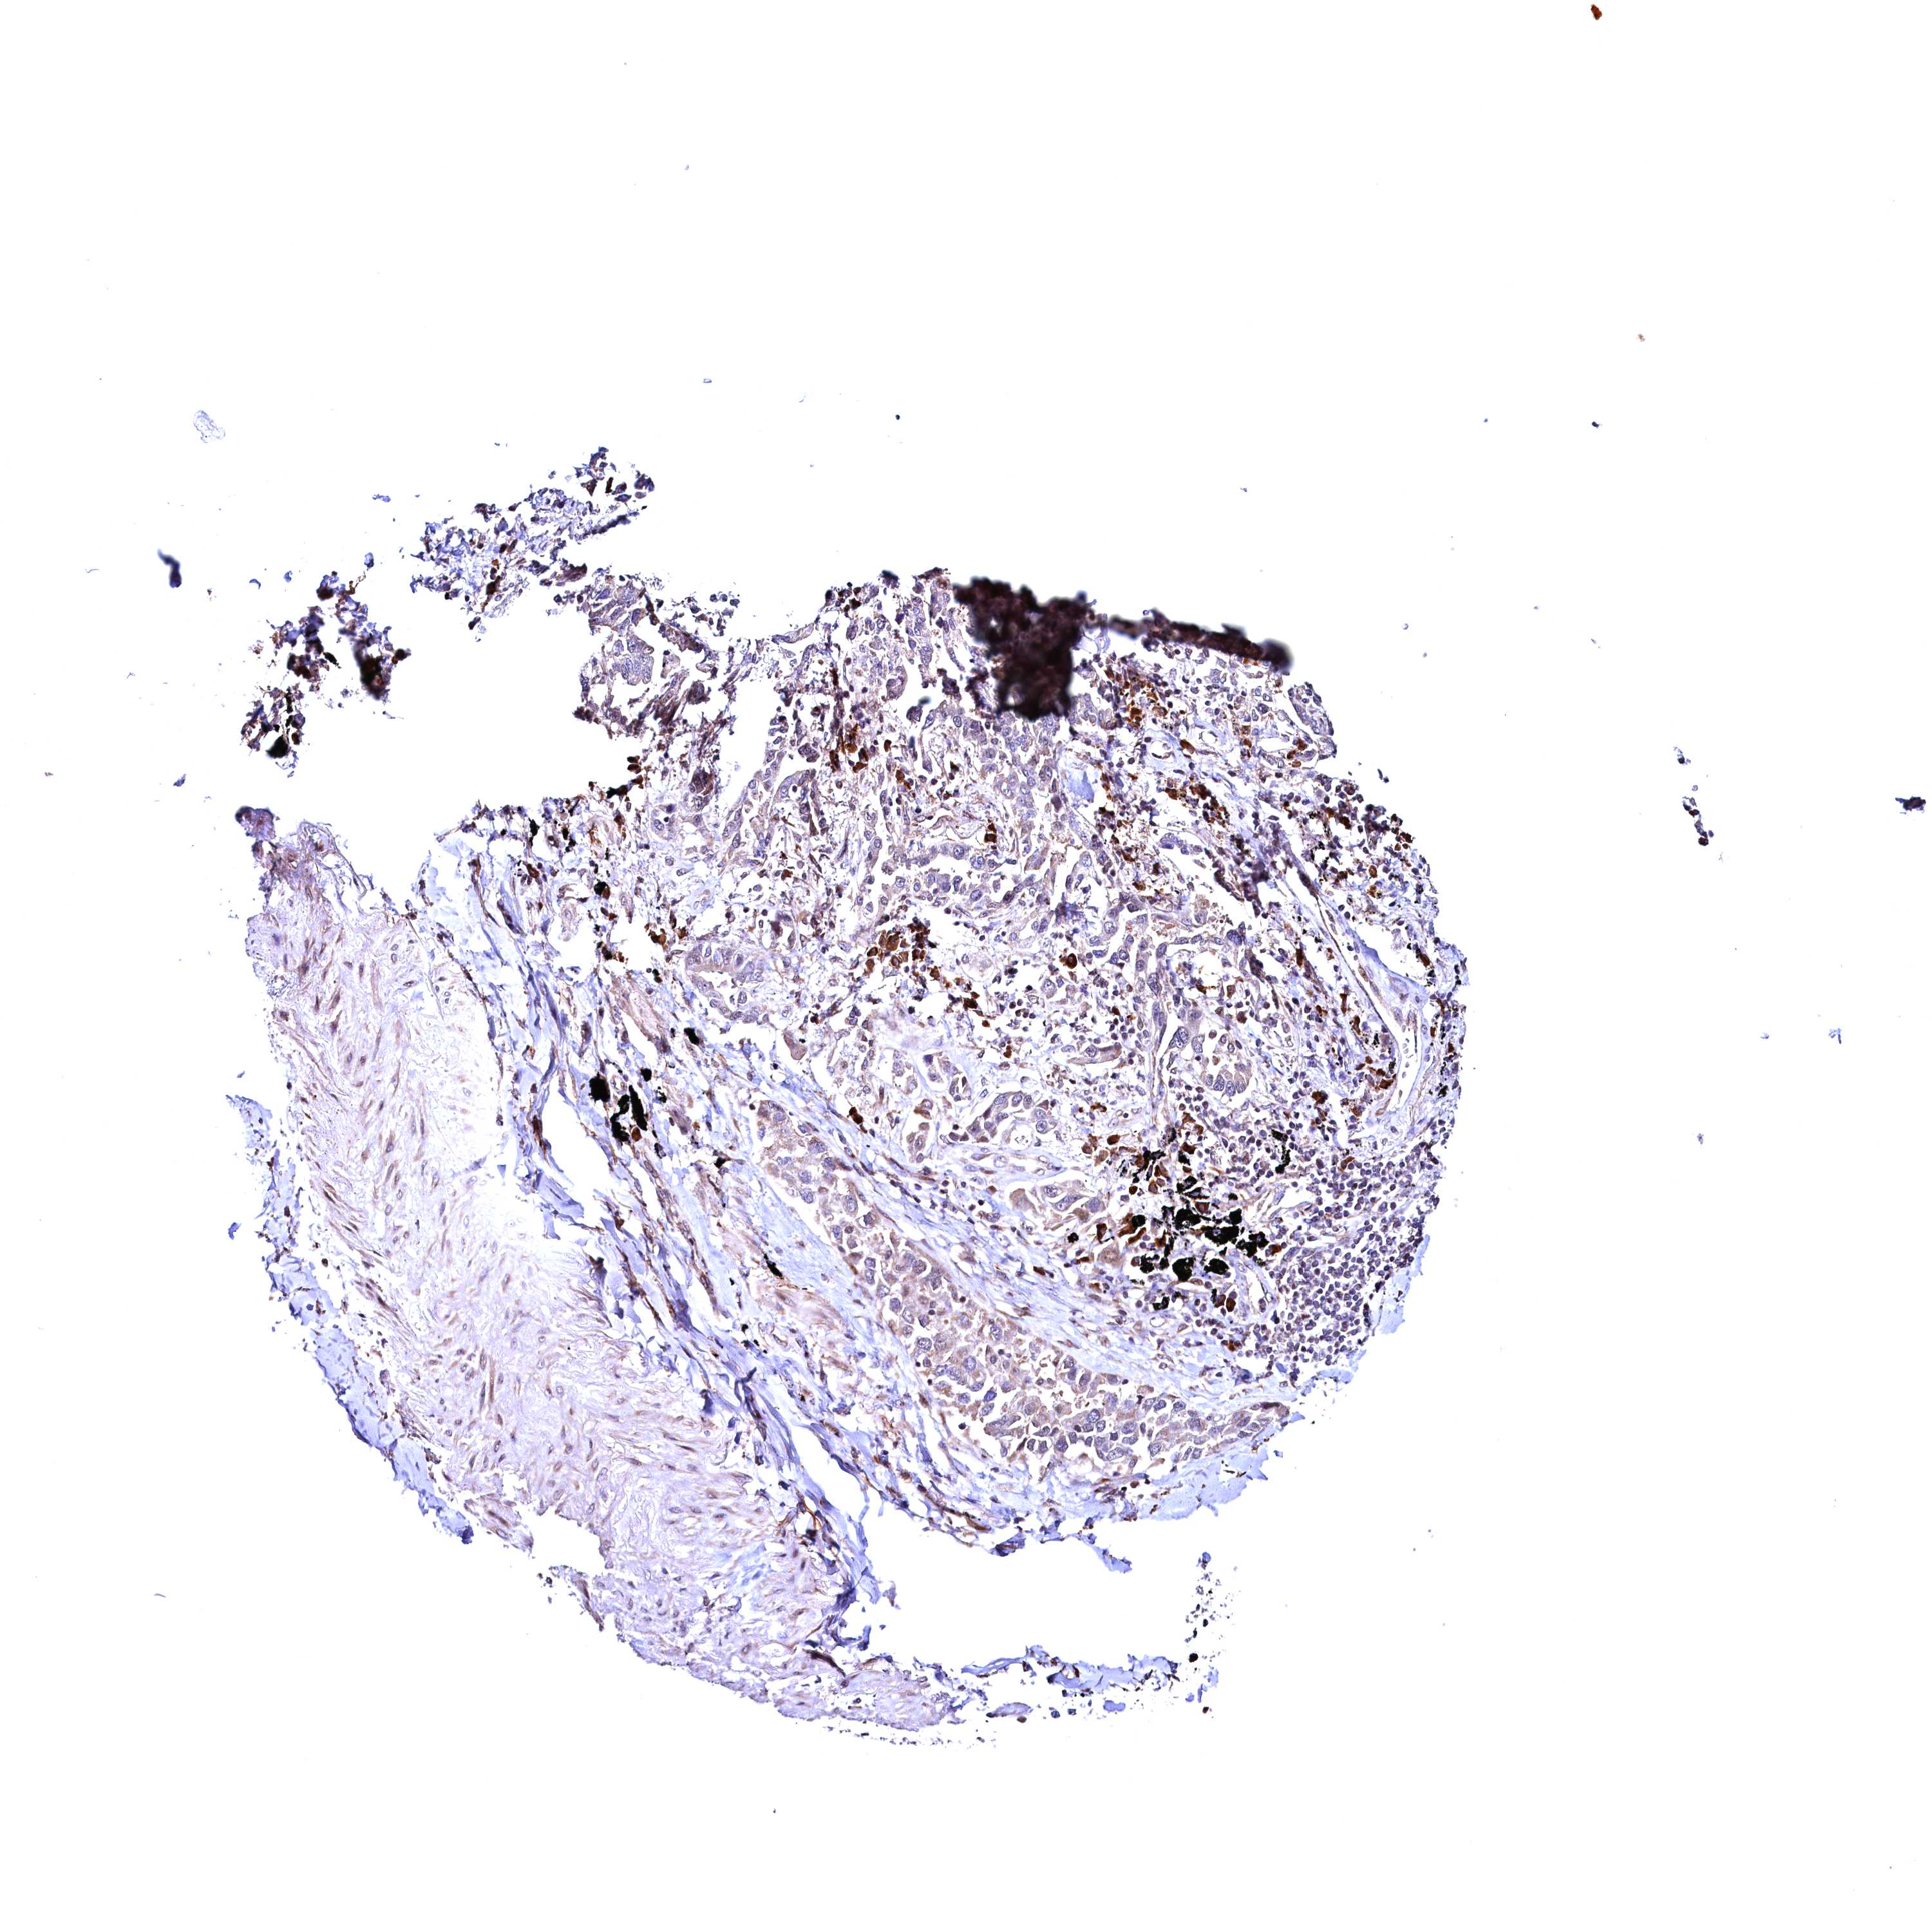

LUNG ADENOCARCINOMA (VALIDATION) - Interactive survival scatter ploti

RBFA is not prognostic in Lung Adenocarcinoma (validation)

Average pTPM 11.6

Number of samples 105